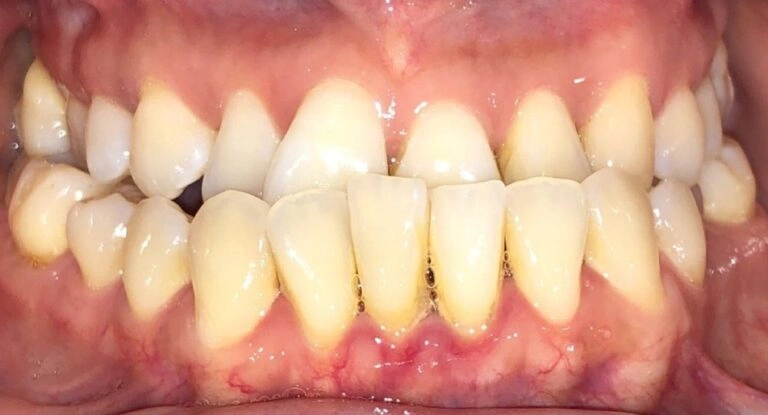

Here’s a visual example of what this looks like:

Patient Example #1: Notice how the teeth are significantly worn down and chipped due to long-term misalignment.

Patient Example #2: A more severe case where untreated deep bites led to significant tooth wear and difficulty chewing.